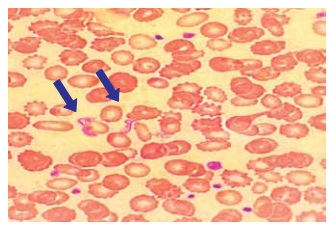

A figura a seguir apresenta um esfregaço de sangue

venoso, em que são visíveis formas características de

um protozoário flagelado. Esse parasita é transmitido por

insetos triatomíneos e está associado a uma doença tropical de grande impacto na América Latina.

(Arquivo pessoal; imagem usada com autorização)

Qual é a doença representada na figura?